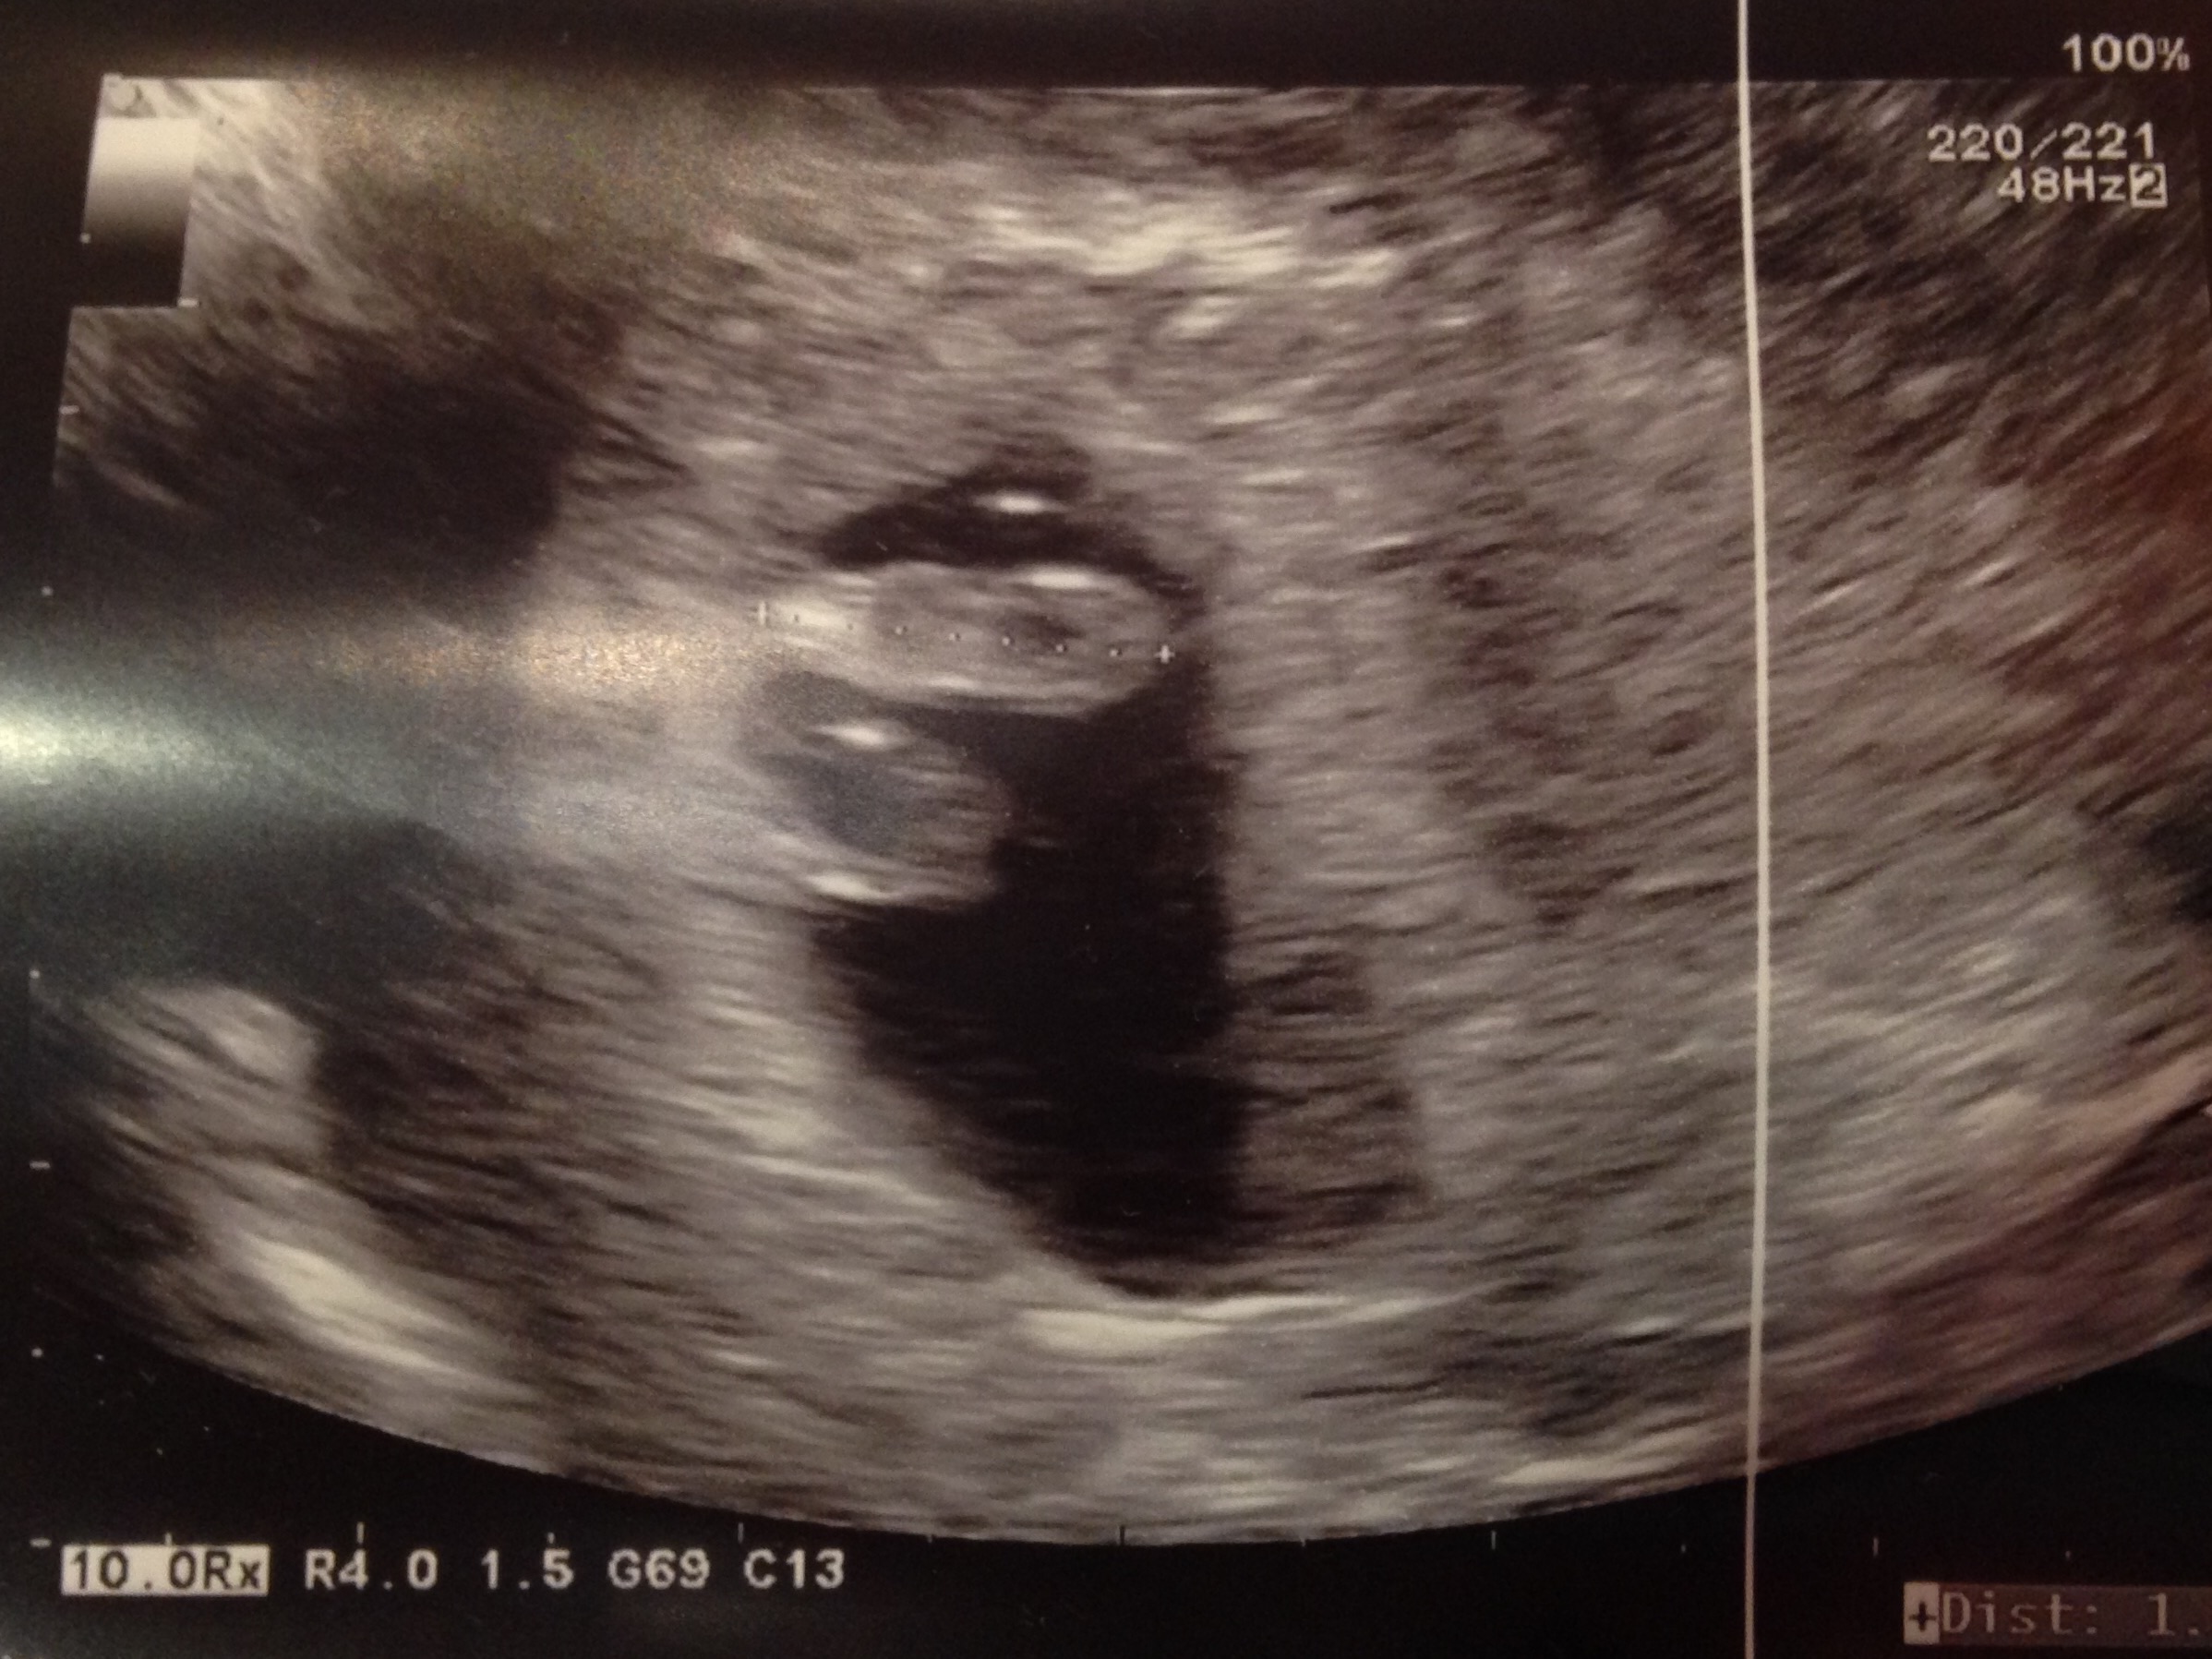

Also Due October. 12th: Our baby bear. 7w3d. Heartbeat 154. transvaginal.

It was amazing. Huz and I cried :)